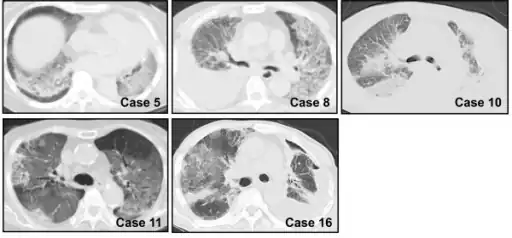

Chest CT images of five persons/cases who developed acute interstitial pneumonia -